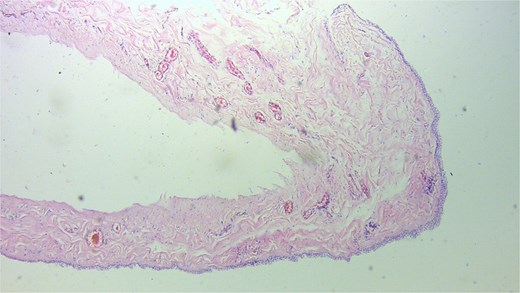

At surgery a cystic lesion was found attached the anterior abdominal wall at the umbilicus, posterior to the fascia (Fig. 2). Blunt and sharp dissection were used to separate the cyst from the anterior abdominal wall towards the bladder, excision of the urachal cyst was done, and the contiguous duct to the bladder excised with a disc of bladder wall tissue. The bladder defect was repaired the abdomen was closed. The bladder was drained continuously for 10 days. Histology confirmed a urachal cyst (Fig. 3).